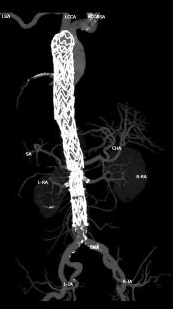

近日,桂林医科大学第二附属医院胸心血管外科团队为一名复杂胸腹主动脉瘤患者实施了“胸腹主动脉覆膜支架腔内隔绝术+腹主动脉四分支全腔内重建术”

该术式采用微创入路,在完整隔绝瘤体、杜绝破裂风险的同时,精准保障了内脏区重要分支动脉的血流通畅。目前,患者术后恢复顺利,已康复出院,回归正常生活。

此次因腰部胀痛再次入院,CT检查显示为原胸主动脉支架远端夹层动脉瘤较前进展,且瘤体已非常接近腹腔干、肠系膜上动脉开口及双肾动脉。

手术团队通过导管导丝操作技术,依次对腹腔干、肠系膜上动脉、双肾动脉进行精准选入并植入支架,成功完成对重要内脏分支动脉的血运重建。最后,一枚大动脉覆膜支架被精准植入胸降主动脉,与主体支架完美衔接,将夹层动脉瘤完全隔绝于血液循环之外,彻底消除破裂风险。术后最终造影结果显示:夹层动脉瘤隔绝彻底,无内漏发生,腹腔干、肠系膜上动脉、双肾动脉等四支血管血流通畅。